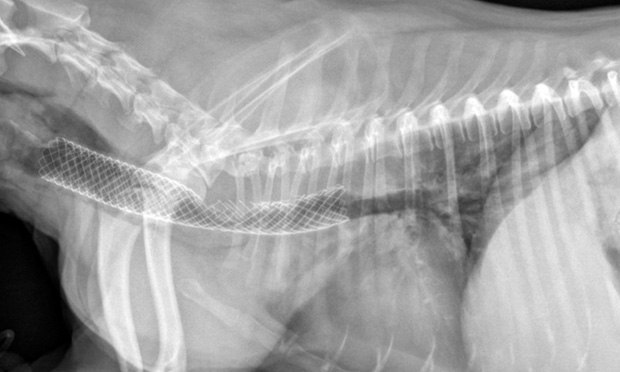

Установка стента, при коллапсе трахеи у собаки.